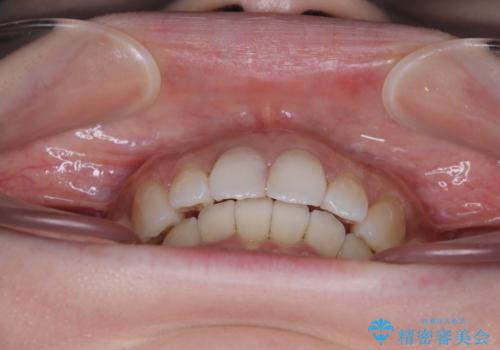

- デコボコと飛び出している前歯を気にして来院された患者様です。

歯列としてはインビザラインでもワイヤー矯正でも対応できるものでしたが、奥歯の咬み合わせを見た時に上顎がやや前方にあり、インビザライン単独では時間のかかってしまう可能性があるため、補助装置を治療当初に使用することで、インビザラインによる治療をスムーズに行えるように計画しました。

インビザラインは得意・不得意の差がはっきりとしているため、補助装置やワイヤー装置などをうまく活用することで、治療期間を短縮するとともに、より理想的な仕上がりを達成することができます。